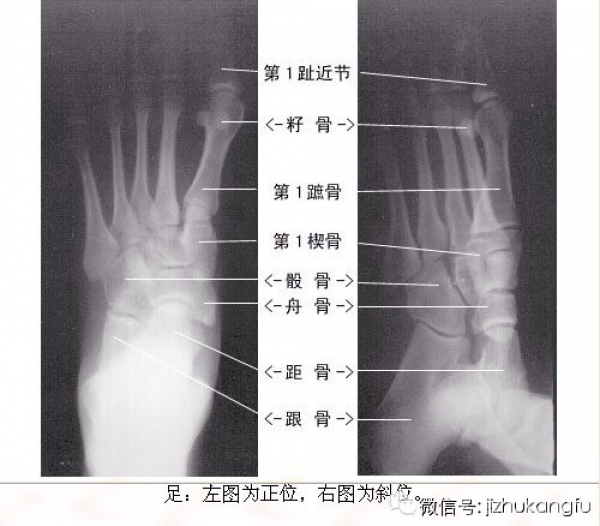

1四肢关节